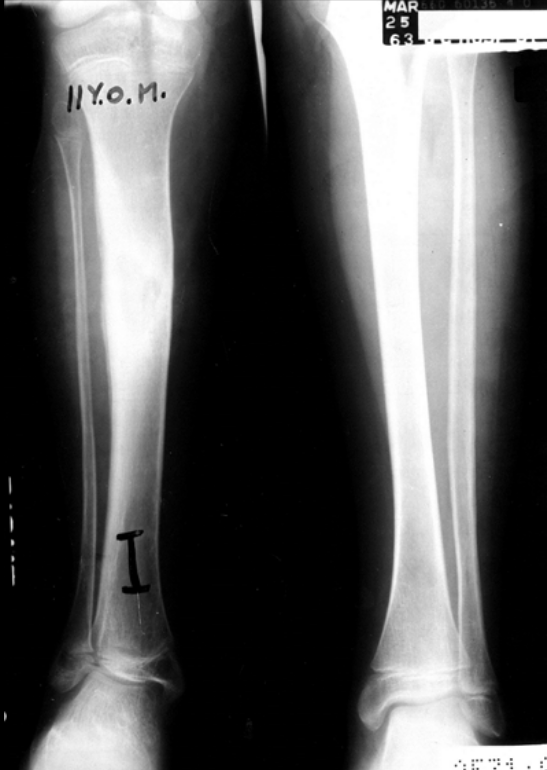

9

Q

11-year-old male presents with chronic leg pain.

What radiographic finding suggests chronic osteomyelitis?

What is the differential diagnosis with this finding?

A

Solid wavy periosteal bone formation

Paget sarcoma

10

12-year-old male presents with chronic leg pain.

What is the diagnosis?

Chronic osteomyelitis

DDx: Paget sarcoma

note solid wavy periosteal bone and cloaca